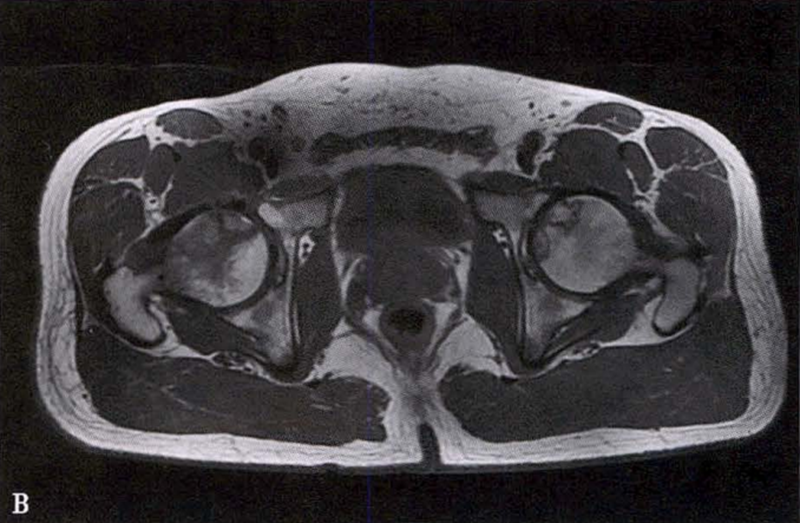

(2)MRI检查 MRI检查是早期诊断股骨头坏死最具特异性、灵敏度的检查方法。当怀疑有股骨头坏死,而X线片无明显异常时,应行MRI检查。诊断时可根据髋关节X线、MRI显示的坏死面积和塌陷程度进行ARCO分期。

冠状面及横断面MRI图像

MRI示双侧股骨头坏死,冠状面显示右侧股骨头坏死(图A、C),横断面显示双侧股骨头坏死(图B、D);T1加权像(图A、B)显示硬化带为低信号,T2加权像(图C、D)显示右侧骨坏死硬化带外围高信号的骨髓水肿,左侧无骨髓水肿。